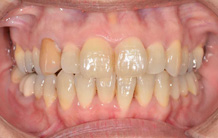

2か月後です。反対咬合は治っています。現在は正常な噛み合せになりました。

これからまだ永久歯に生え替わるので、注意深く定期的に観察していきます。生え替わった後に、また反対咬合になりこともあります。